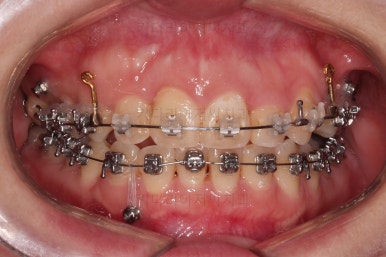

장치 부착 직후의 모습인데요.

보이는 느낌과 장치 때문에 약간 더 튀어나오는 입매 참고 바랍니다.

장치 때문에 입이 나오는 정도는 사람마다 매우 다르므로 실제로 부착해 봐야 아는 경우가 많긴 합니다.

미니스크류를 적절히 사용해서 부정교합도 맞추고 입매도 약간 들어가게 혹은 너무 들어가지 않게 조절해 주고요.

치열의 경사 등등도 조절해 줍니다.

부산부정교합이긴 하지만 애초에 입매가 많이 나쁘진 않았기 때문에 자칫하면 입이 너무 들어갈 수 있어 중간중간 환자분과 상의하여 너무 들어가지 않게끔 조절해 줍니다.

적절하게 틈도 다 모아주고요.

디테일을 정리하고 마무리를 하게 됩니다.